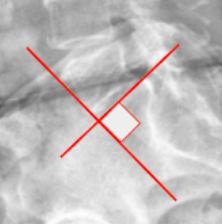

Ferguson’s Line

Ullman’s Line

Mcnab's Line